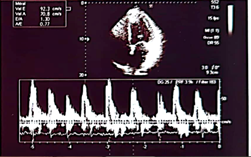

Case number 1: This is a 60-year-old male patient with a history of known hypertension for 10 years controlled with Candesartan plus hydrochlorothiazide 32/25 mg daily. Mixed dyslipidemia controlled with statin type atorvastatin 40 mg daily. Significant central obesity BMI of 35. Also, sedentary life. History of 4 inoculations with the Pfizer vaccine, he began to present with acute respiratory distress, palpitations, paroxysmal nocturnal dyspnea, orthopnea, saturation of 85% by oximetry. On physical examination: marked arterial hypotension 80/60 FC: 135 beats per minute Respiratory rate of 28 per minute acrocyanosis and on cardiac auscultation: rhythm Irregularly irregular with a more audible mitral regurgitation murmur at the apex of the heart radiating to the axilla. Lung auscultation: crackles from the middle third to the base of both lung fields. The electrocardiogram shows rapid atrial fibrillation rhythm at 135 beats per minute. Chest X-ray: Grade III-IV cardiomegaly with acute pulmonary edema. An echocardiogram was performed, showing findings compatible with dilated cardiomyopathy with left ventricular ejection fraction of 10%. Global hypokinesia, in doppler moderate-severe mitral regurgitation. Moderate-severe tricuspid regurgitation with pulmonary systolic pressure of 90 mmHg. Tissue Dopplar significant increase in left intraatrial pressure 25. In addition, the following laboratory analyzes were performed: Complete blood count: leukopenia: 2,000 leucocytes. Hb: 12.5 g/dl. Thrombocytopenia: 107,000 platelets, severe eosinopenia and lymphopenia. Elevated D-dimer 2.0 (normal value up to 0.50) Elevated NtproBNP 3,500 (normal up to 300). C-reactive protein of 32 Normal up to 10. Ferritin of 750 (normal up to 250). Creatinine: 3.2 mg/dl Urea: 70, TGO: 110, TGP:115.

Echocardiogram

Severe

1. Findings compatible with dilated cardiomyopathy secondary to graphene hydroxide

2. Severely depressed ejection fraction (10%).

3. Moderate-severe mitral regurgitation

4. Elevated left intraatrial pressure (20)

5. Ventricular filling pattern of a restrictive nature

6. Moderate pulmonary arterial hypertension

7. Fast Atrial Fibrillation Rhythm.